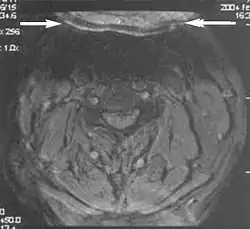

A wrap-around artifact also known as an aliasing artifact, is a result of mismapping of anatomy that lies outside the field of view but within the slice volume.[4] The selected field of view is smaller than the size of the imaged object. The anatomy is usually displaced to the opposite side of the image (Figs 6 and 7). It can be caused by non-linear gradients or by undersampling of the frequencies contained within the return signal.[1] The sampling rate must be twice the maximal frequency that occurs in the object (Nyquist sampling limit). If not, the Fourier transform will assign very low values to the frequency signals greater than the Nyquist limit. These frequencies will then ‘wrap around’ to the opposite side of the image, masquerading as low-frequency signals. In the frequency encode direction a filter can be applied to the acquired signal to eliminate frequencies greater than the Nyquist frequency. In the phase encode direction, artifacts can be reduced by an increasing number of phase encode steps (increased image time). For correction, a larger field of view may be chosen.[1]